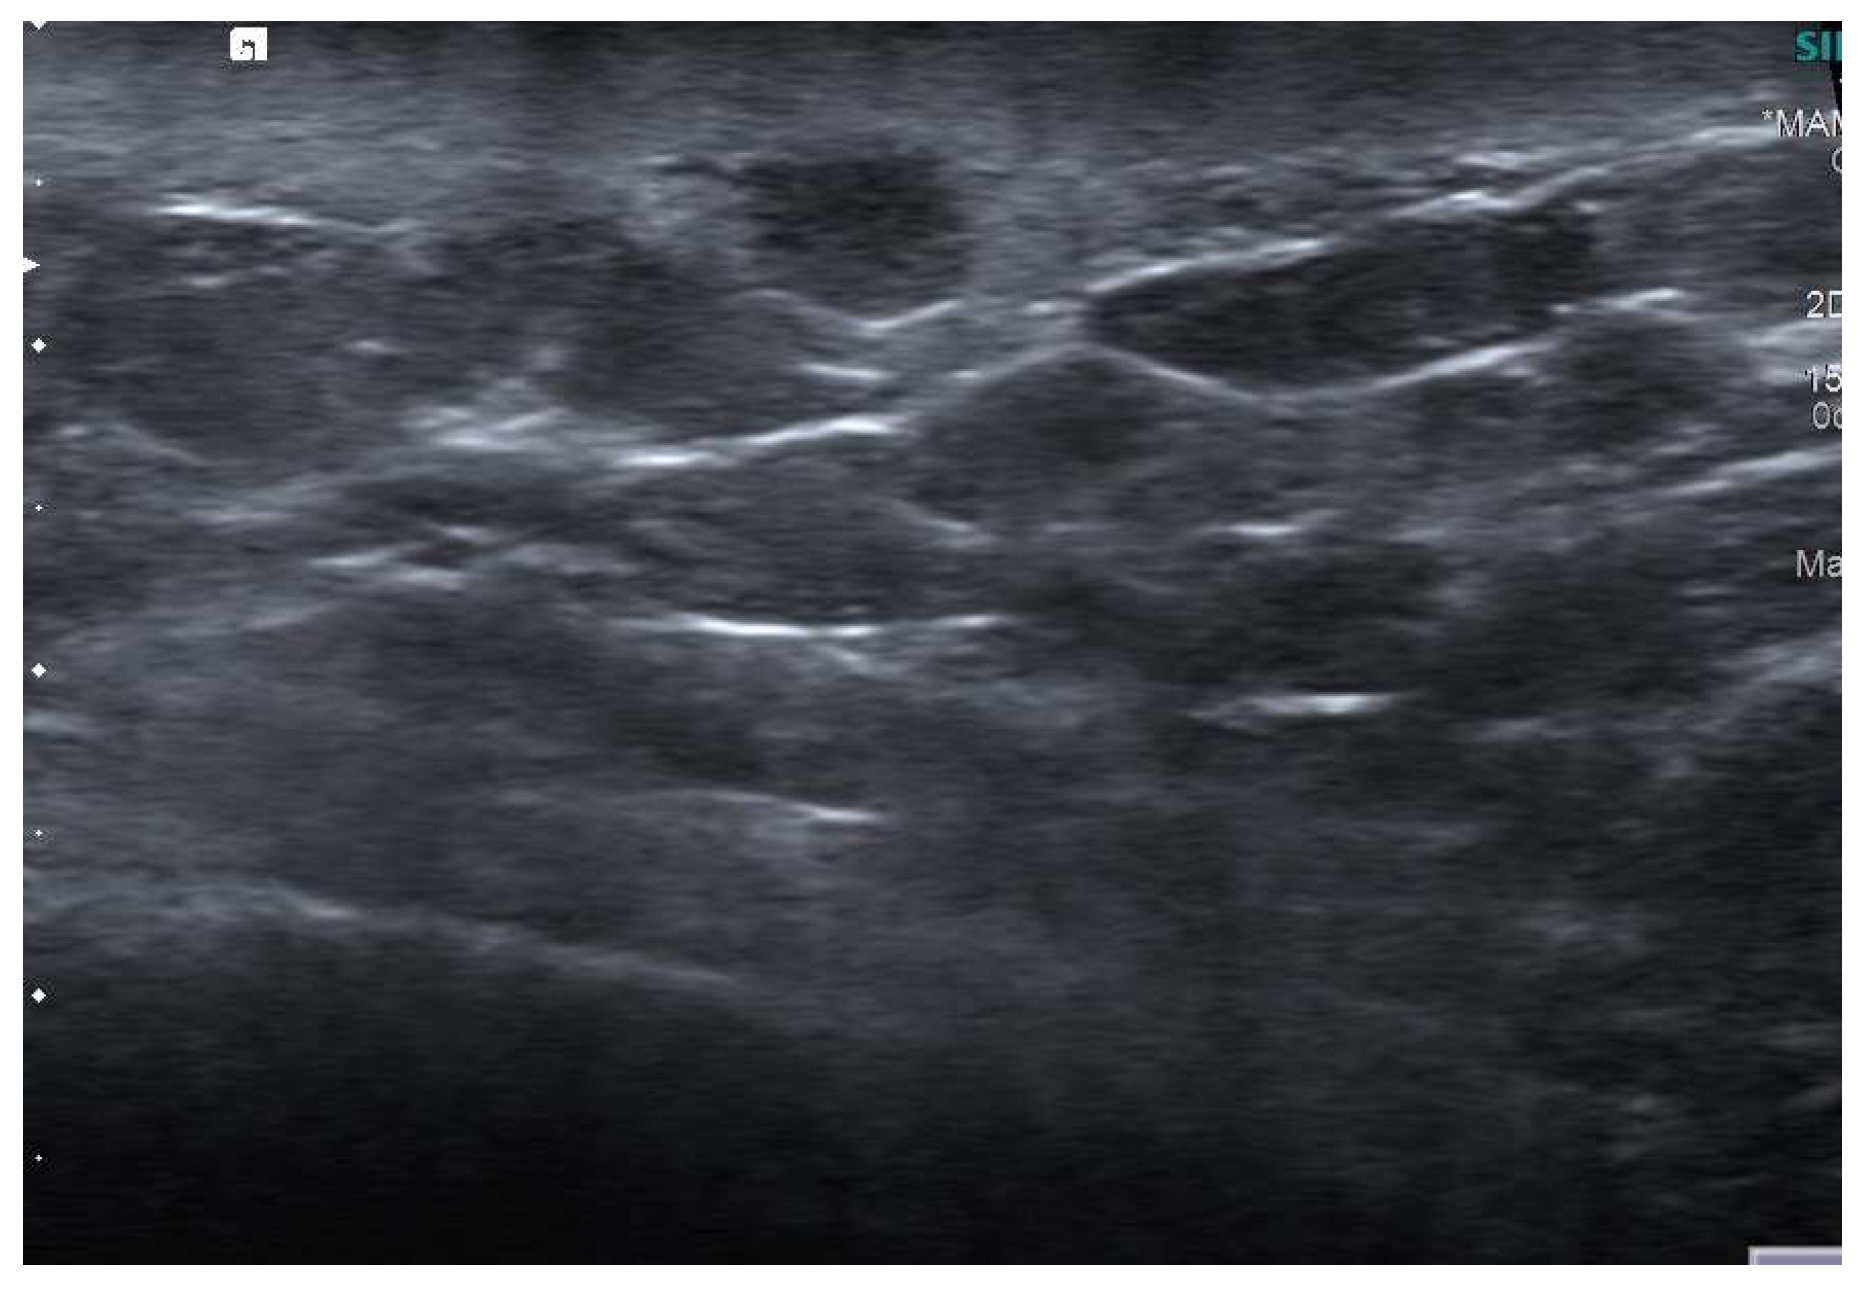

4.2. Ultrasound